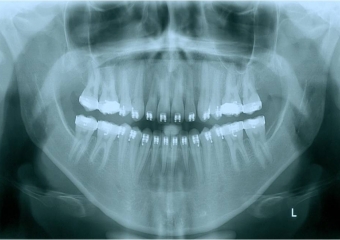

Raio x inicial

Raio x após a cirurgia